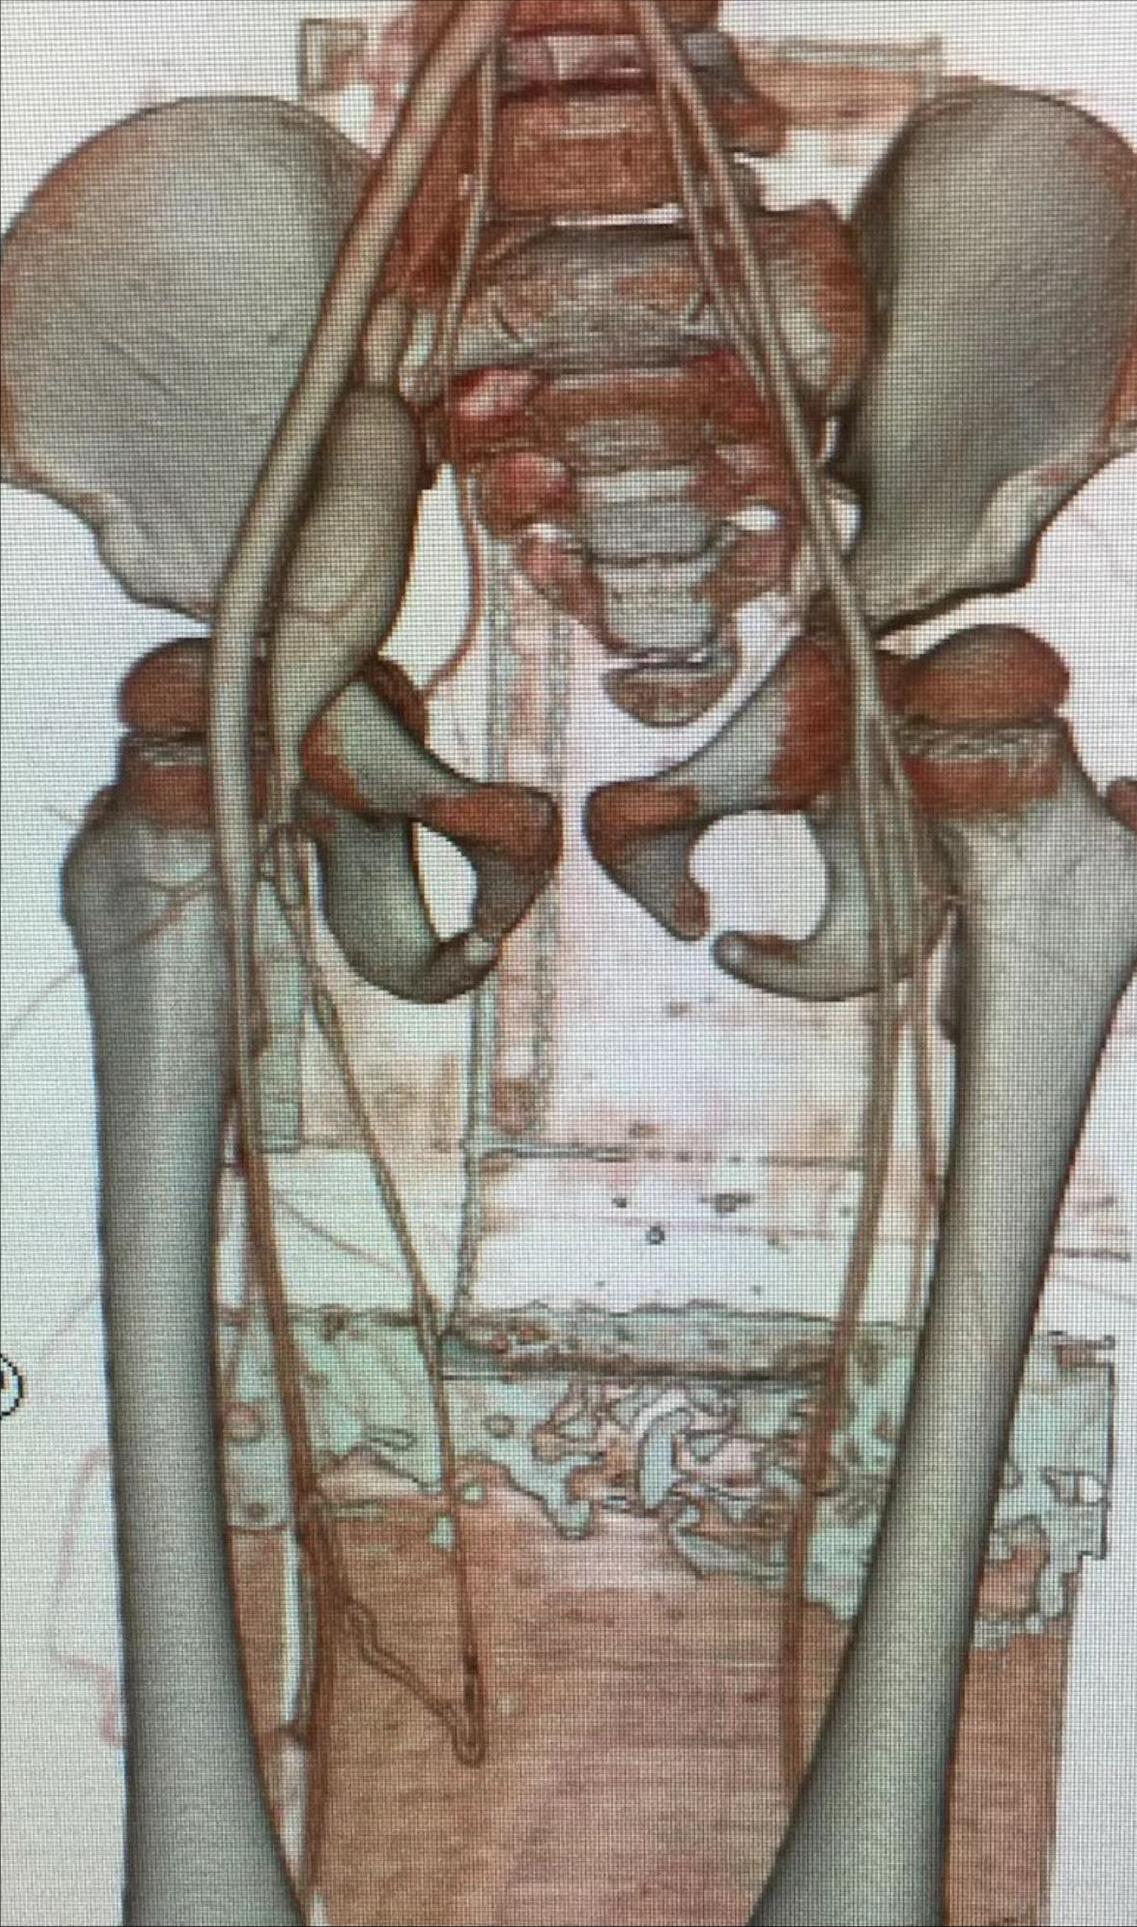

患儿是一对双胞胎,三岁的小女孩,就诊前一年发现右下肢肿胀,温度升高,表面静脉曲张,当地医院CTA检查考虑动静脉畸形,罕见的先天股浅动静脉瘘(见图)。

术前CT血管造影可见瘘口